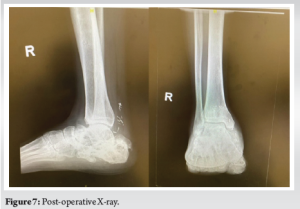

There was good restoration of calcaneal width, height, and alignment as well as subtalar and calcaneocuboid joint congruency. The critical-sized bone defect was adequately addressed with the use of the synthetic scaffold in conjunction with the Masquelet “induced membrane” technique incorporating autogenous iliac crest bone graft and BMAC. At 3 years post-operation, the patient is ambulant without walking aids, reports minimal pain, and remains infection-free. The surgical wounds are well healed, and the flap is healthy (Fig. 6). Repeat radiographs and CT scans show callus formation, bony fusion, and graft incorporation (Fig. 7 and 8). While there is some degree of interval collapse of the calcaneal height as well as subtalar and calcaneocuboid arthritis, the use of the synthetic scaffold provided a significant restoration of height as compared to the index injury radiographs.